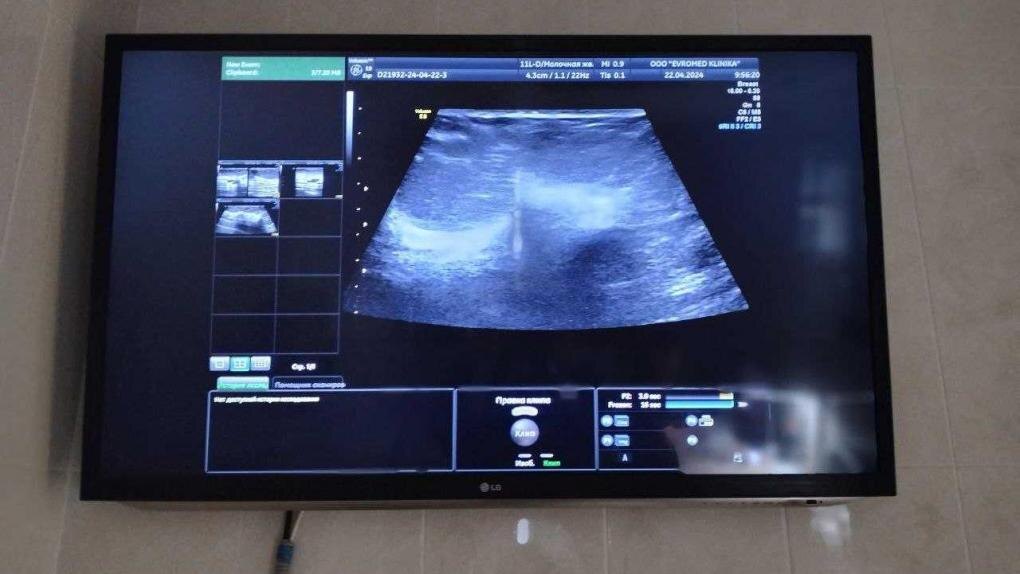

«Я забеременела в 17 лет от парня, с которым встречалась три года. Мне сделали кесарево, сказали, что родилась девочка. И это первая странность: на УЗИ мне говорили, что у меня будет мальчик. Потом врач, принимавшая у меня роды, заявила: «Ты родила монстра! Она не выживет». А спустя три дня мне сказали, что мой ребёнок умер», — рассказала КП-Новосибирск Дарья.

Есть и другой момент: на снимке у врача, принимавшей роды, Дарья увидела мальчика, очень похожего на родственников её бывшего парня. Может ли он как-то быть связан с историей — для Дарьи этот вопрос остаётся открытым.